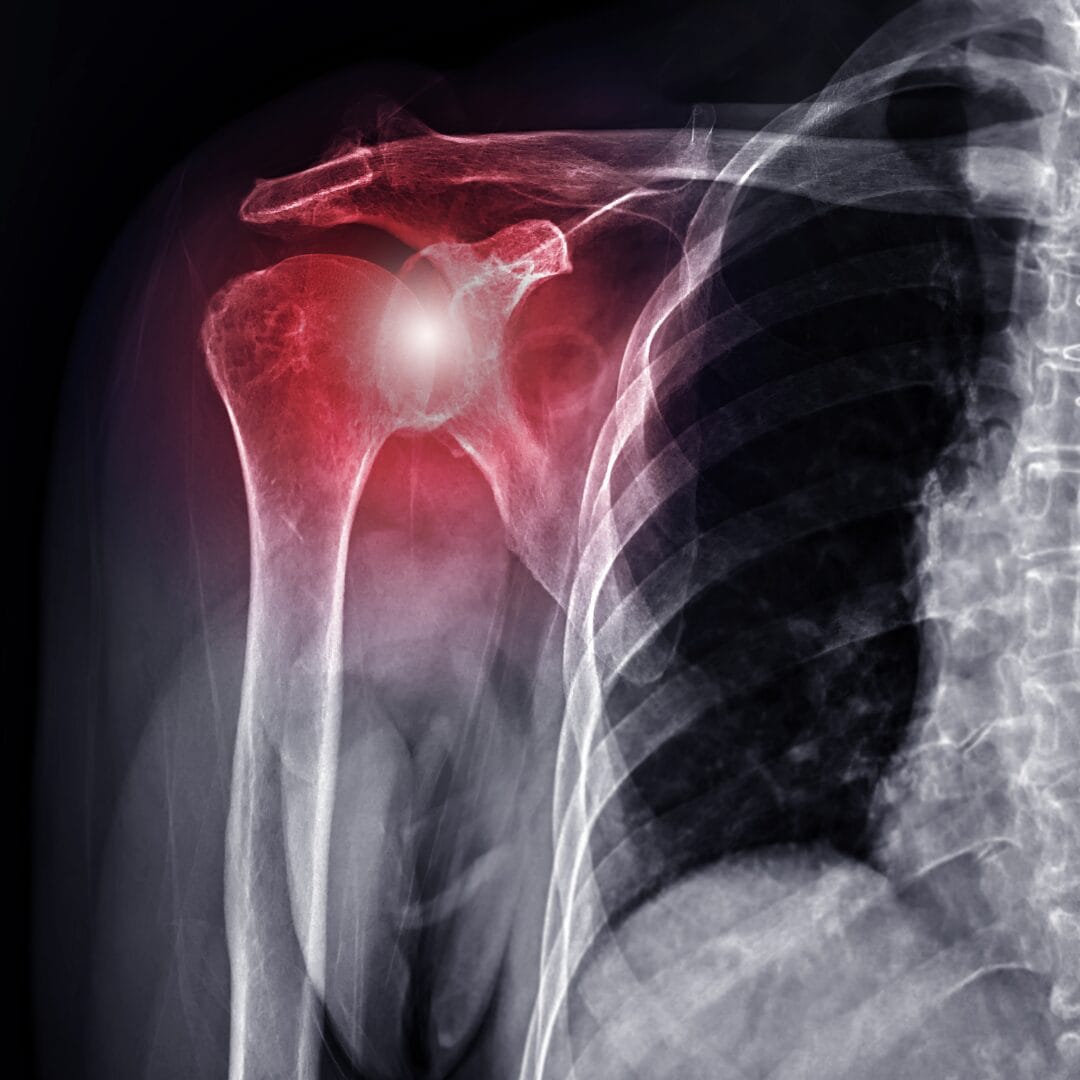

Frozen Shoulder: Causes, Stages and When Surgery Is the Answer

A shoulder that gradually becomes too painful and stiff to lift, reach, or rotate — that is what frozen shoulder feels like. It often starts slowly and gets worse over weeks or months, until even simple tasks like combing hair or reaching for something on a shelf become difficult.

Frozen shoulder — medically called adhesive capsulitis — happens when the tissue surrounding the shoulder joint tightens and thickens. This restricts movement and causes pain. It is not simply a muscle problem or a posture issue. The joint capsule itself becomes inflamed and contracted, which is why it needs proper medical evaluation rather than self-management alone.